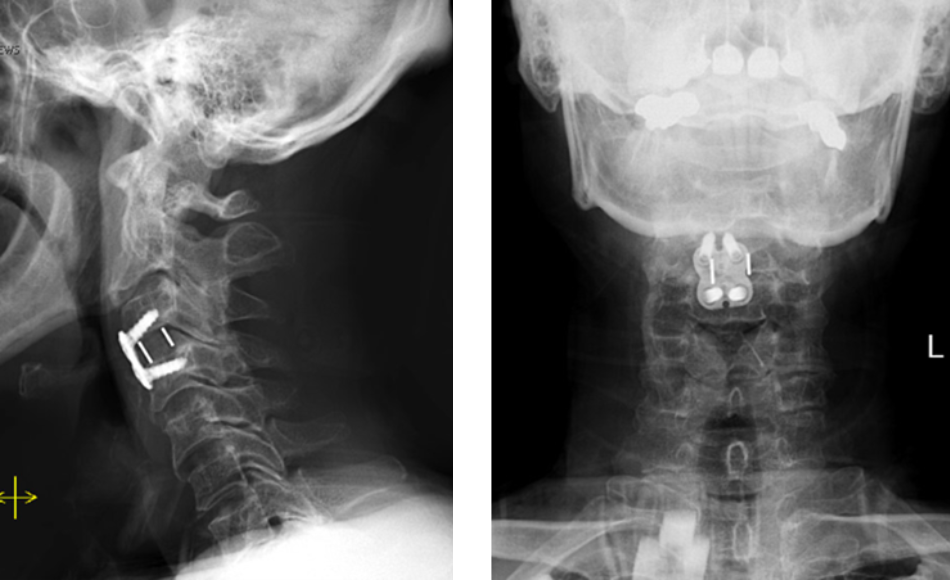

This is a 42-year-old otherwise healthy male who presented electively with progressively worsening neck pain radiating down the left arm, with paresthesia first three digits. He […]